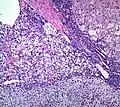

Histopathology

The microscopic histopathology analysis of the tissue samples obtained from the adrenal cortex of individuals presenting with adenoma-associated symptoms such as primary aldestronism (PA) indicates that adenoma cells are relatively larger with different cytoplasm, and increased variation in nuclear size. This indication is based on comparison between the healthy (normal) and affected (adenoma-associated) adrenal cortex tissue samples.

- Adrenocortical adenoma with focal high grade nuclear atypia

- Adrenocortical adenoma with focal necrosis